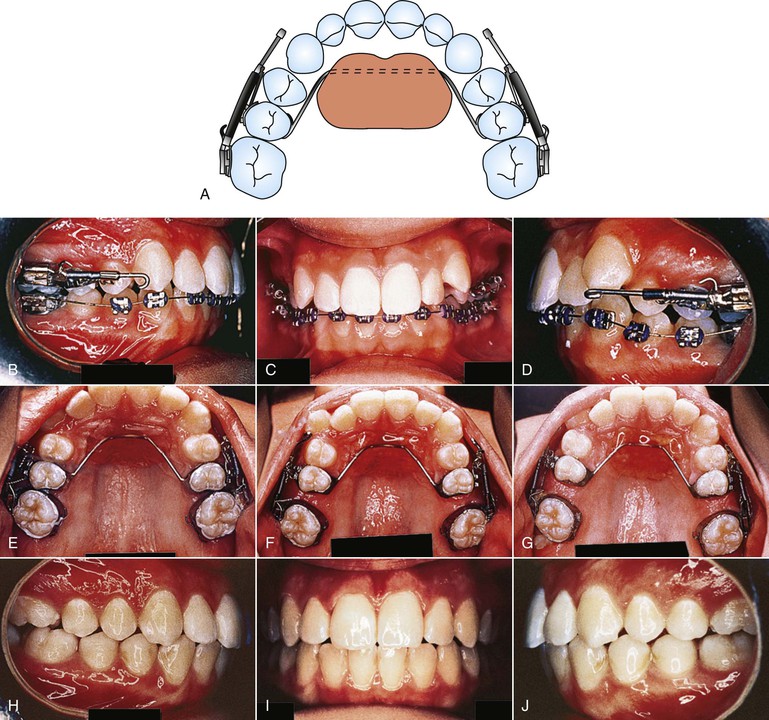

Figure 12-11 Jones jig appliance. A, Schematic of the modified Nance appliance banded to the second bicuspids with the Jones jig assemblies tied into place. B–D, Pre-treatment photographs of a patient with a Class II, Division 1 malocclusion, showing the activated appliance. E-G, Intraoral palatal photographs at (from left to right) initial delivery (0 months), 2 months, and 4 months of appliance activation. H–J, Treatment completion. Total treatment time was 24 months. The majority of the time was spent distalizing the premolars, canines, and incisors.